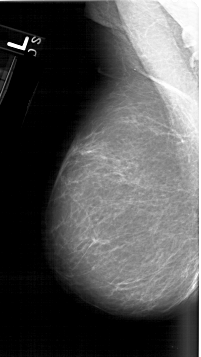

A_1610_1.LEFT_MLO

LEFT_MLO LINES 6421 PIXELS_PER_LINE 3601 BITS_PER_PIXEL 12 RESOLUTION 43.5 NON_OVERLAY